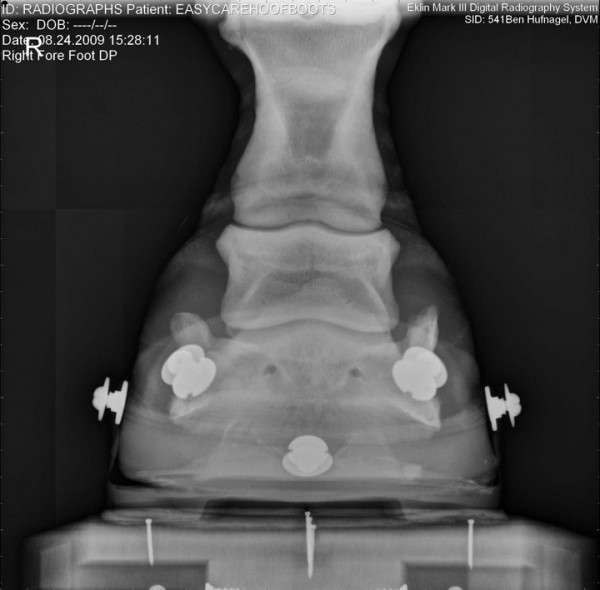

Společnost EasyCare si dělá vlastní průzkumy-výzkumy… zde jsou zajímavé fotografie jak to vypadá když je kopýtko v botě, zůstává ve svém přirozeném tvaru, kopytní mechanismus je neomezený a kůň ho má možnost plně přirozeně využívat 🙂